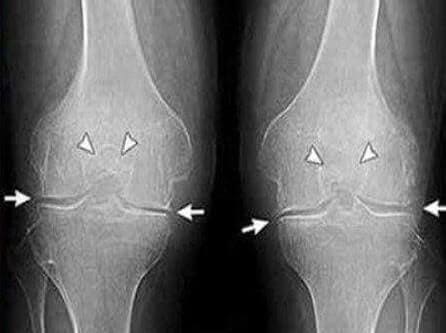

Как ни верти, а пришлось идти к врачу, жена моя настояла на этом. Терапевт отправил меня к ревматологу, попасть к которому мне удалось через месяц с лишним, очередь, однако, не один я суставами маюсь, нас таких оказалось много. Встретила меня ну очень пожилая врач, ничего не говоря отправила меня на рентген и анализы крови/мочи. На втором приеме за пару минут поставила мне диагноз — какой-то артроз, первичный или вторичный, сейчас уж точно не помню, да и не важно это.

35 день: сдал анализы и сделал рентген. Никаких следов артроза! Хрящи в суставах как у 30-ти летнего пацана. Докторша сказала, что на предыдущем рентгене скорее всего был дефект, поэтому диагноз артроз был ошибочным.